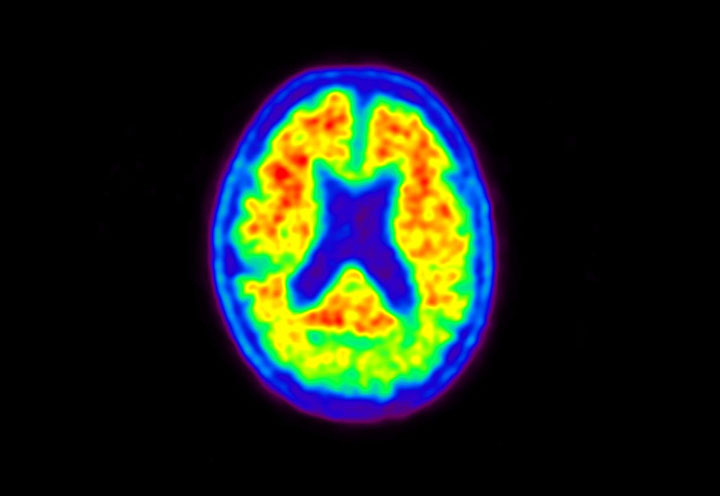

Head / Case5 : Amyloid

Sagittal

Courtesy : Kindai University Hospital

- Imaging protocol

- Injected dose: 4.27 MBq/kg, 18F-Flutemetamol

- Uptake time: 99 minutes

- Scan time: 20 minutes